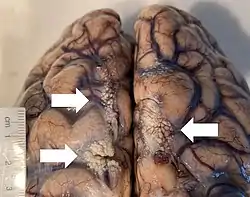

Arachnoid granulations seen on autopsy, where the dura mater has been removed but the arachnoid mater is left in place. | |

Arachnoid granulations (also arachnoid villi, and pacchionian granulations or bodies) are small protrusions of the arachnoid mater (the thin second layer covering the brain) into the outer membrane of the dura mater (the thick outer layer). They protrude into the dural venous sinuses of the brain, and allow cerebrospinal fluid (CSF) to exit the subarachnoid space and enter the blood stream.

The largest granulations lie along the superior sagittal sinus, a large venous space running from front to back along the center of the head (on the inside of the skull). They are, however, present along other dural sinuses as well.